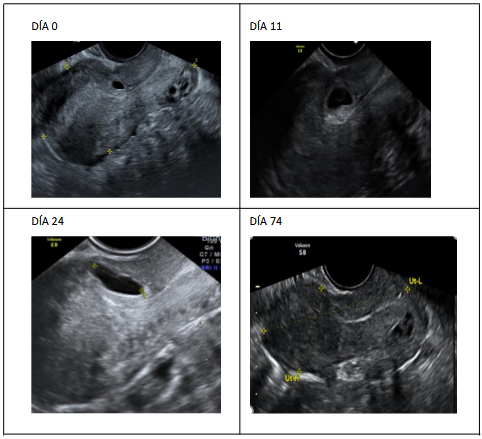

Mujer de 43 años actualmente con antecedente de G5P3023, G1 parto vaginal, G2 cesárea por distocia de cordón, G3 parto vaginal, G4 aborto más legrado uterino por gestación no evolutiva, G5 embarazo en cicatriz en cesárea. En esta última gestación acudió a consulta por embarazo en cicatriz con saco gestacional de 8.2 mm, vesícula vitelina presente, asociado a HCG- β: 3,455 UI, 2 días después presenta HCG-β de 4,616 UI por lo que se hospitaliza, día 0, Figura 1, y se inicia metotrexato a dosis única de 50 mg/m2 de superficie corporal, al 4to día presenta HCG-β de 6, 043 UI al 7mo día HCG- β de 4,000 UI (disminución de 34%) presentando ecografía con gestación en cicatriz de cesárea: saco gestacional 9x6 mm, vesícula vitelina de 5mm, esbozo embrionario sin latidos, se repite dosis de metotrexato, saliendo de alta. Se monitoreó hasta el día 74 (Figura 1) con ecografía que evidencia imagen sacular en regresión de 5.8 x 6.7 mm.

Figura 1 Evolución de la imagen ecográfica del caso 1